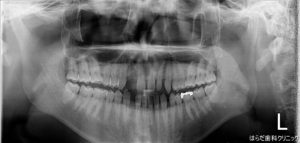

こちらはインプラントを埋入する前のレントゲンの写真です。

写真は左右反転しているので反転させてご覧ください!

スペースが空いている前歯の箇所にインプラントを埋入していきます。